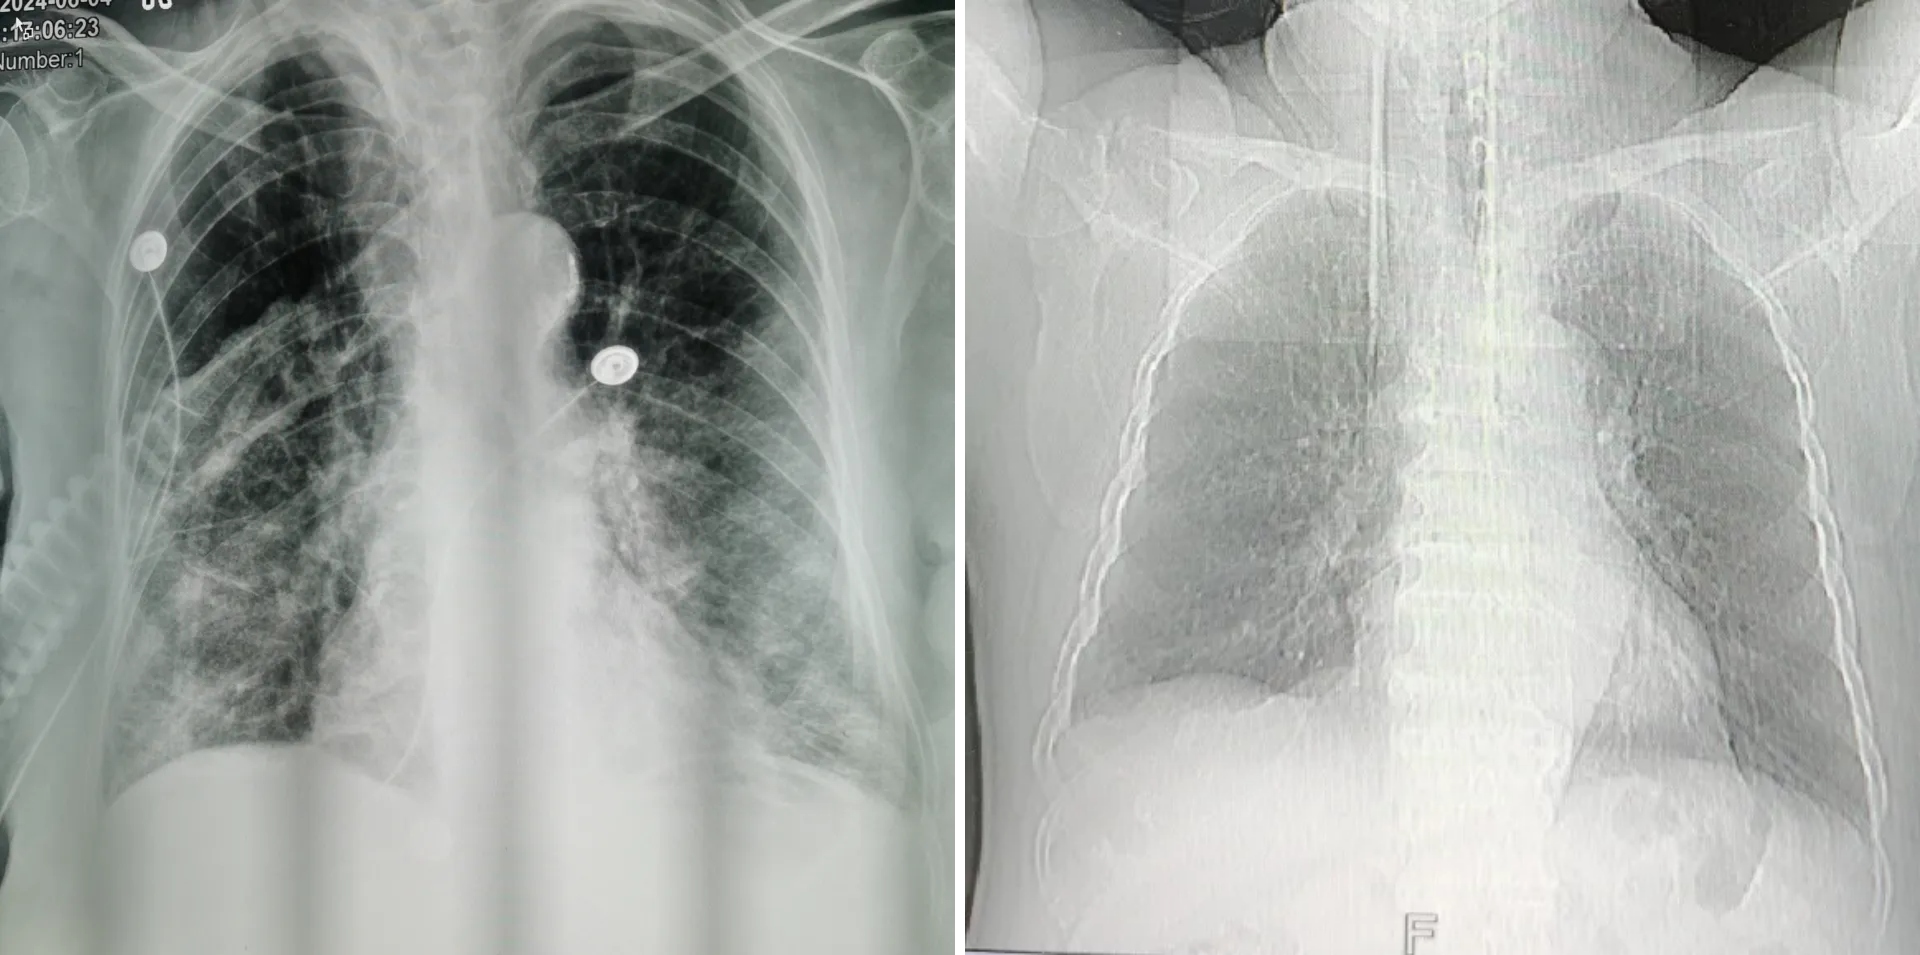

▲治疗前(左)、治疗后(右)

ICU医护团队第一时间召开紧急病例讨论会,为马阿姨制定了精密的治疗方案。在动态复查血气、关注炎症、凝血、肝肾功能及电解质水平的基础上,予无创呼吸机辅助呼吸,提高氧供,改善氧合,减轻心脏负荷。结合床旁胸片给予静滴以防止感染,配合雾化吸入降低气道炎症,改善气道痉挛,帮助患者祛痰……5日后,复查结果显示,马阿姨恢复良好,不仅意识清楚,精神状态也好了起来,能够顺畅地和医护进行交流。看到马阿姨转危为安,家属悬着的心终于放下了。